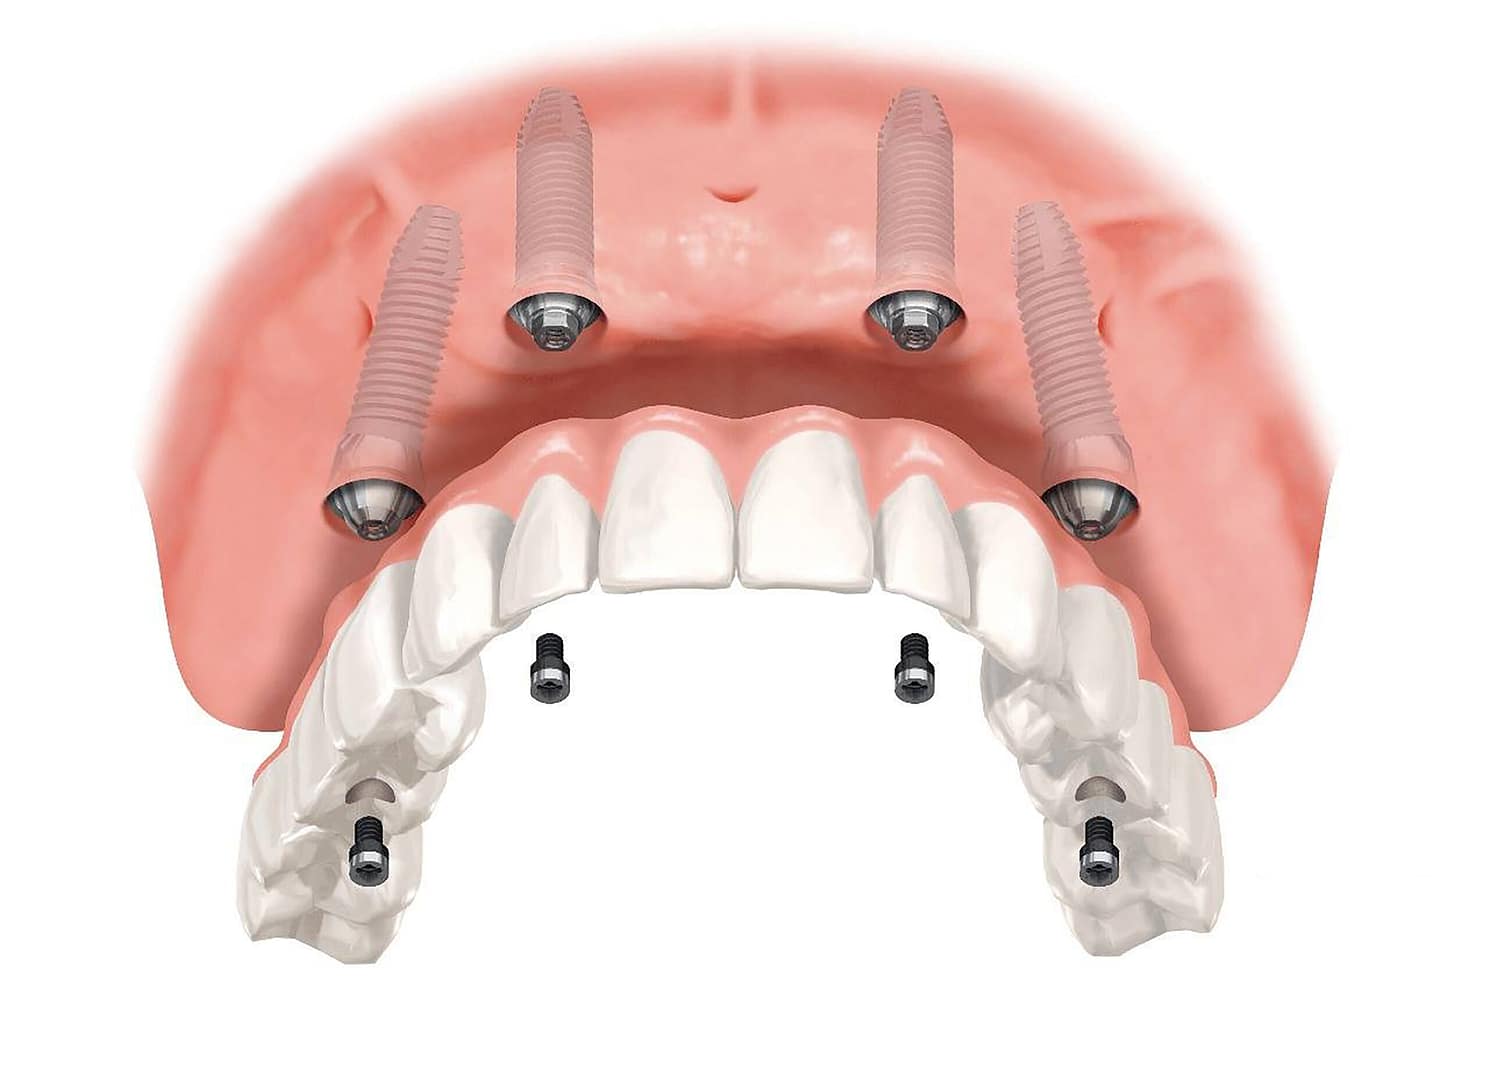

Hoy en día, los implantes dentales “hechos en Perú” ofrecen la misma seguridad y calidad que los tratamientos internacionales, combinando tecnología avanzada, especialistas capacitados y protocolos adaptados al paciente peruano.

Tecnología de punta

- Radiografías digitales y tomografía 3D: planificación precisa del implante.

Los implantes dentales realizados en Perú cumplen estándares internacionales, respaldados por tecnología avanzada, especialistas capacitados y un enfoque humano.